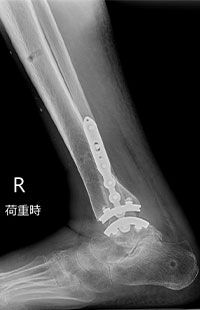

足くびの人工関節に加えて、足くびの中心にある「距骨(きょこつ)」という骨をセラミック製の「人工距骨」に置き換えます。セラミック製の人工距骨は強度が高く、生体とのなじみも良いです。

人工距骨の設計は、患者さんそれぞれのCT画像をもとに設計・製造された完全オーダーメイドです。完成までに2ヵ月程度かかります。

術前

術後